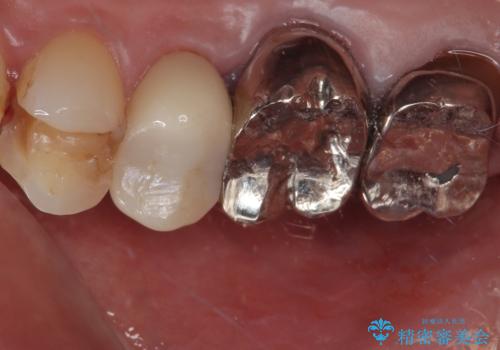

- 「右上の第一小臼歯の詰め物が外れてしまった」という主訴でご来院されました。

診査したところ、既存の詰め物の一部が欠け、歯と詰め物の境目にも段差がある状態で、再度詰め直しが必要でした。